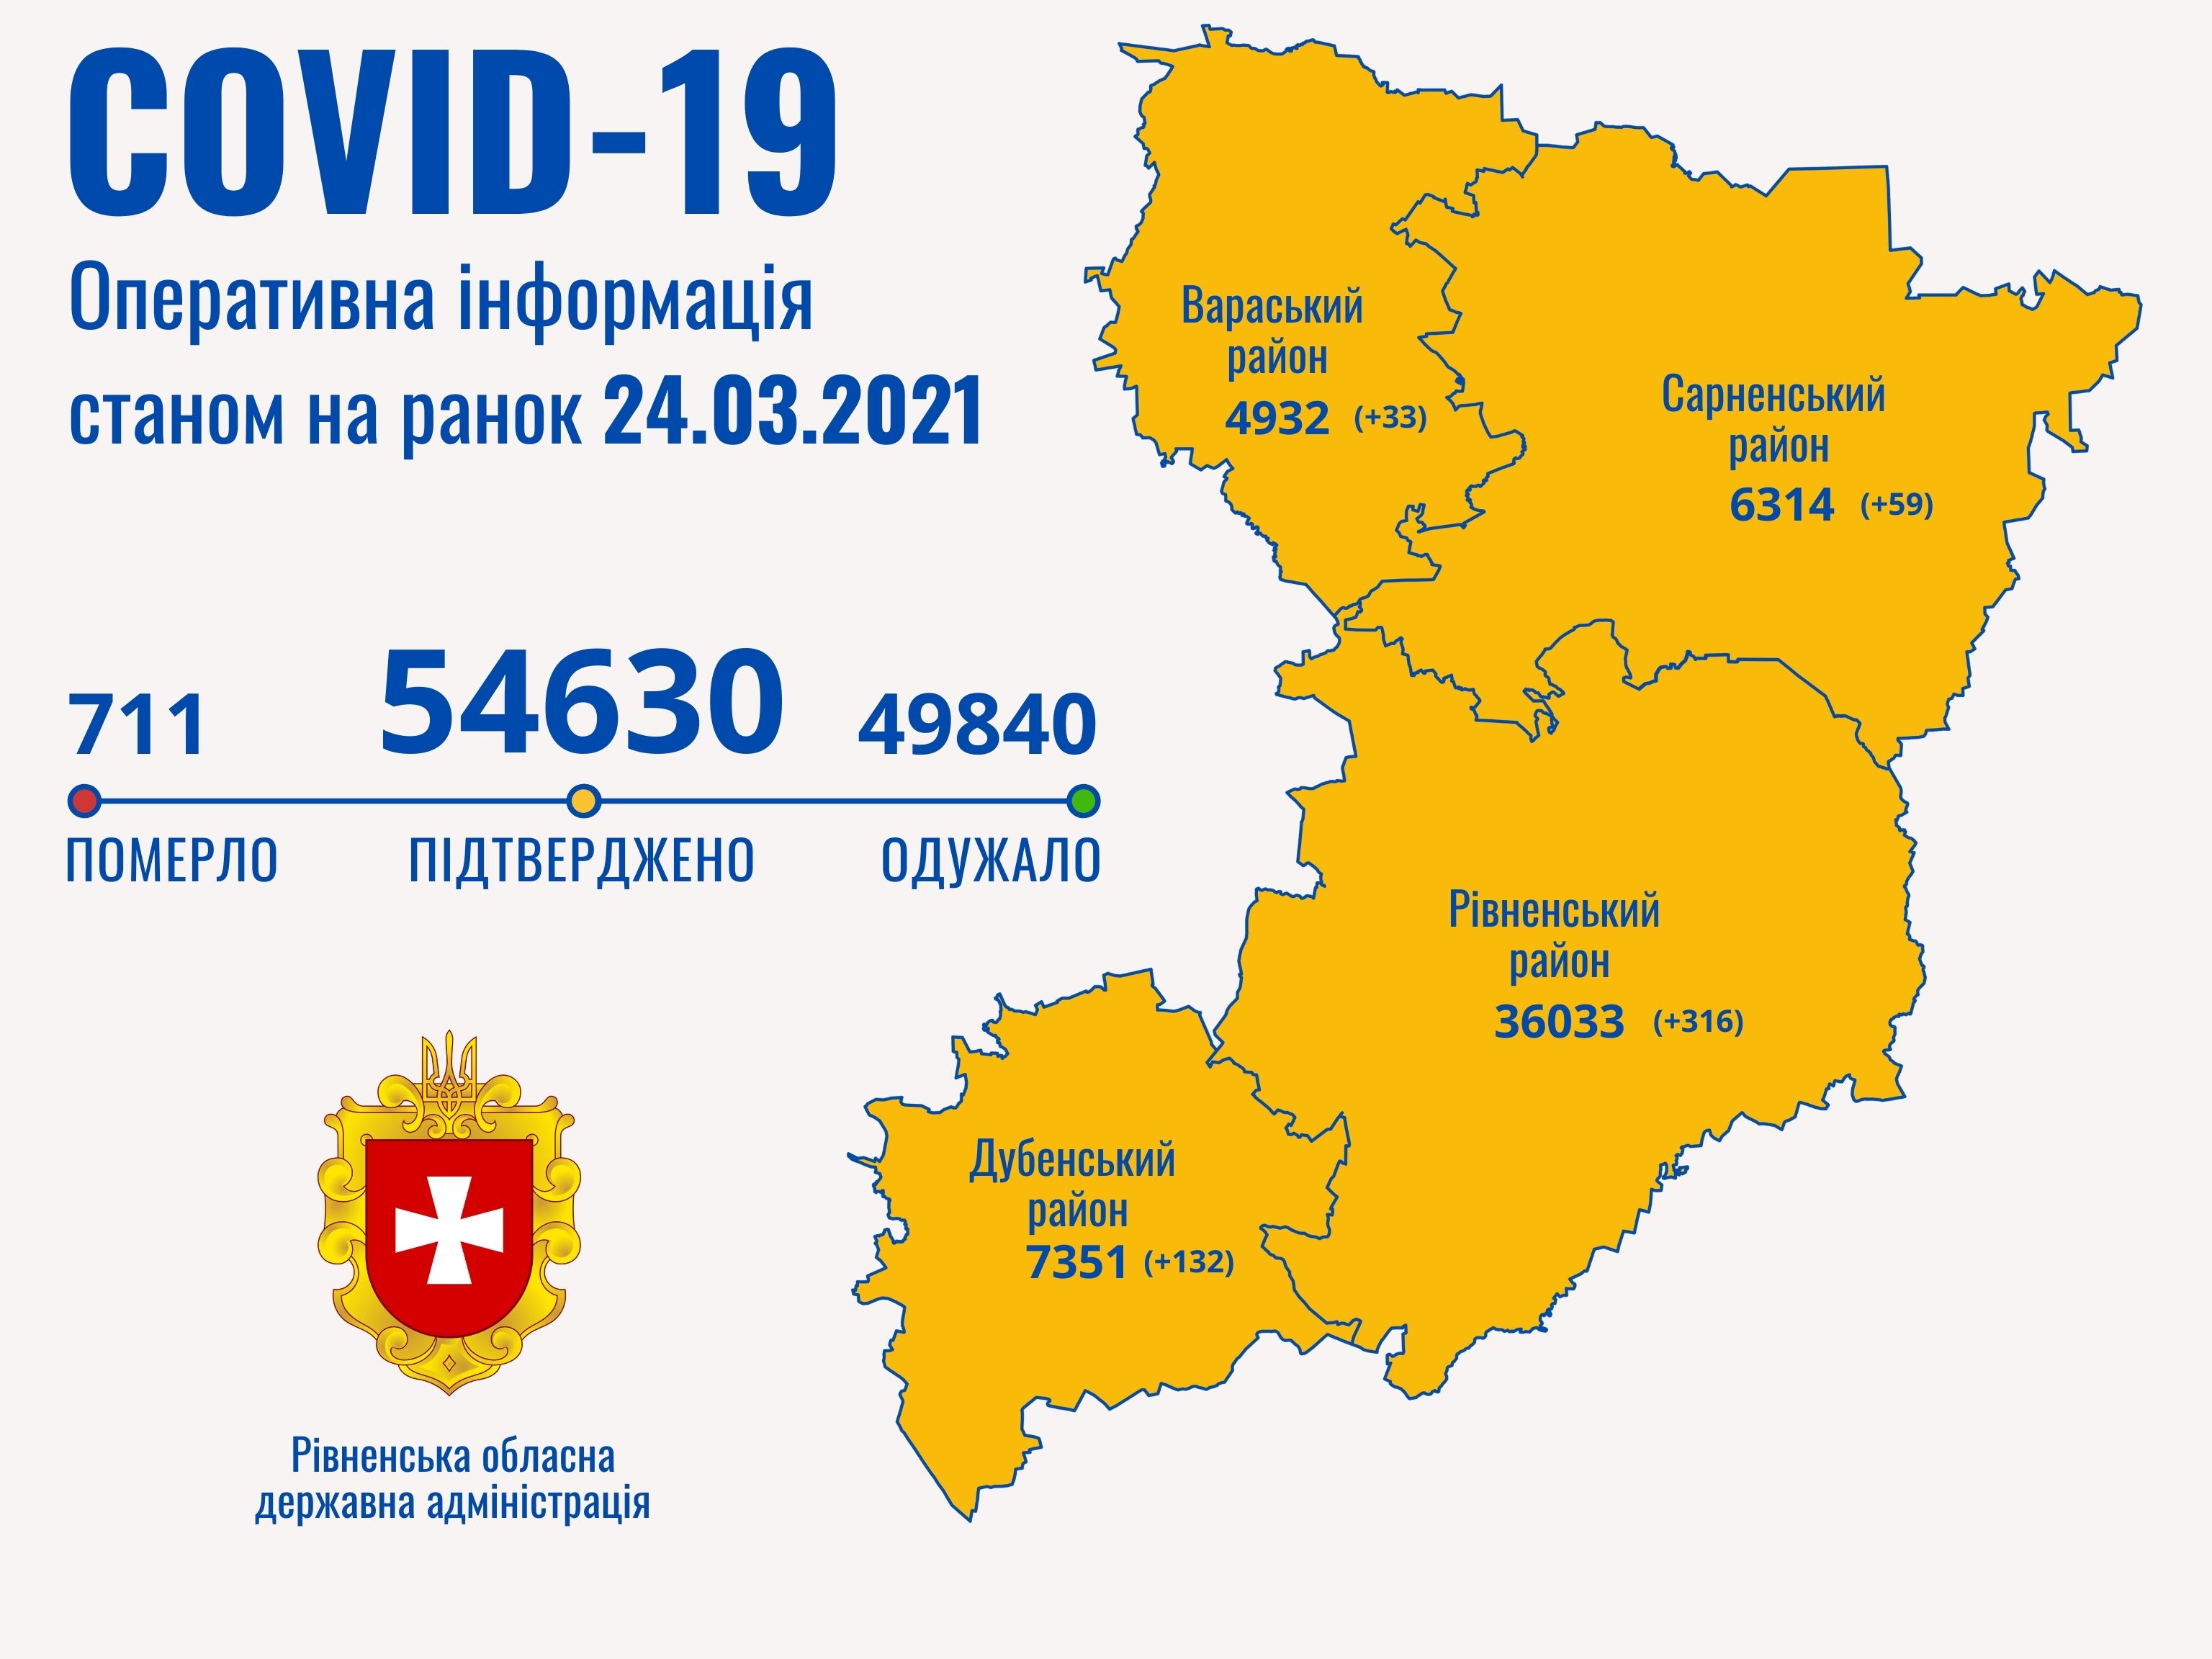

Коронавірус повертається: як стрімко зростає кількість хворих на Рівненщині (ВІДЕО)

Пів тисячі - у важкому стані, 9 жителів Рівненщини померли за добу від коронавірусу